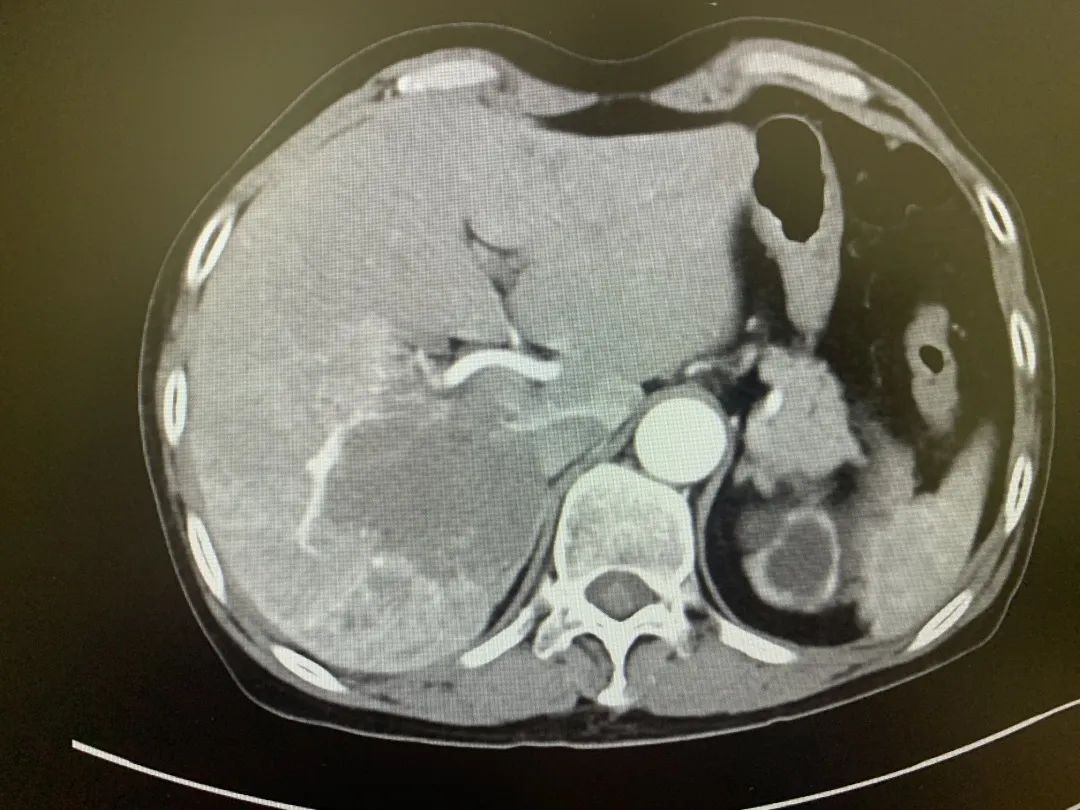

术后CT

手术结束以后,了解到自己的瘤体会不断缩小,患者的脸上也挂上了久违的微笑,同时也向郝萍主任竖起了大拇指,对重庆西区医院的专业治疗表达了感谢和称赞。

郝主任介绍:肝血管瘤介入栓塞术,是通过栓塞供血动脉后瘤体内可形成血栓,血栓机化、纤维化使瘤体形成纤维瘤样结构而达到缩小、硬化血管瘤的目的,具有创伤小、恢复快、费用相对低等特点。手术过程中,由于患者肝动脉迂曲,导致导管难以进入,于是采取了微导管超选的方式进行介入治疗。